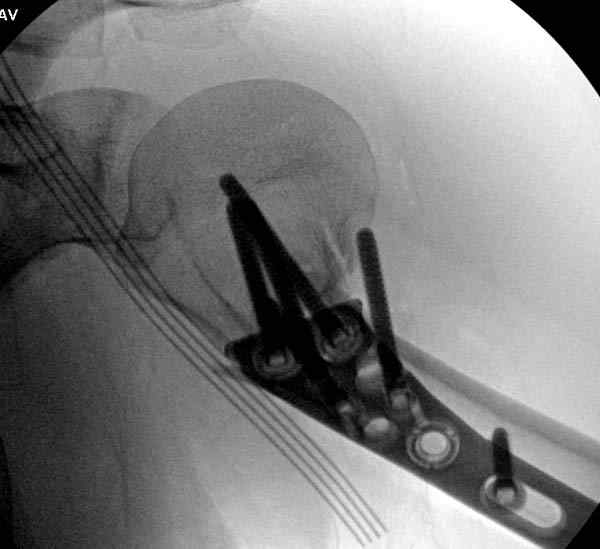

Здесь пример открытой репозиции 57 летнего с переломом плеча (1,2) смещение обнаружено на интероперационном снимке. При нормальной прямой проекция (3) угловое смещение обнаружили в аксиальной проекции (4)

После устранения смещения пластина установлена выше (5,6,7) и финальные снимки (8,9,10)

Подбор импланта тоже имеет значение, например многие импланты направлены для фиксации перелома без учета ротаторной манжетки. Предпочтительными являются низко сидящие полиаксиальные пластины, где верхние шурупы можно проводить под углом в 120 градусов. (11)